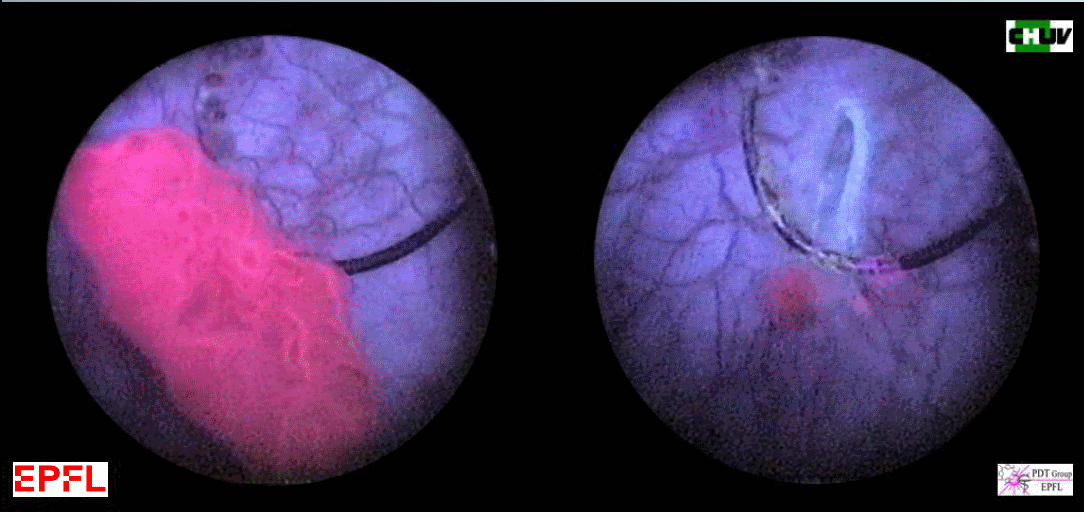

Photodetection of flat lesions (Carcinoma in-situ) in the bladder with white light (left) and ALA-Hexylester fluorescence cystoscopy (right).